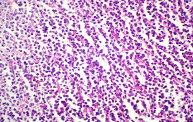

T cell lymphomas : deals in detail with latest WHO classification; histogenesis with regard to steps of development of T cells; the various subtypes; morphology; differential diagnoses and IHC markers of T cell lymphomas.